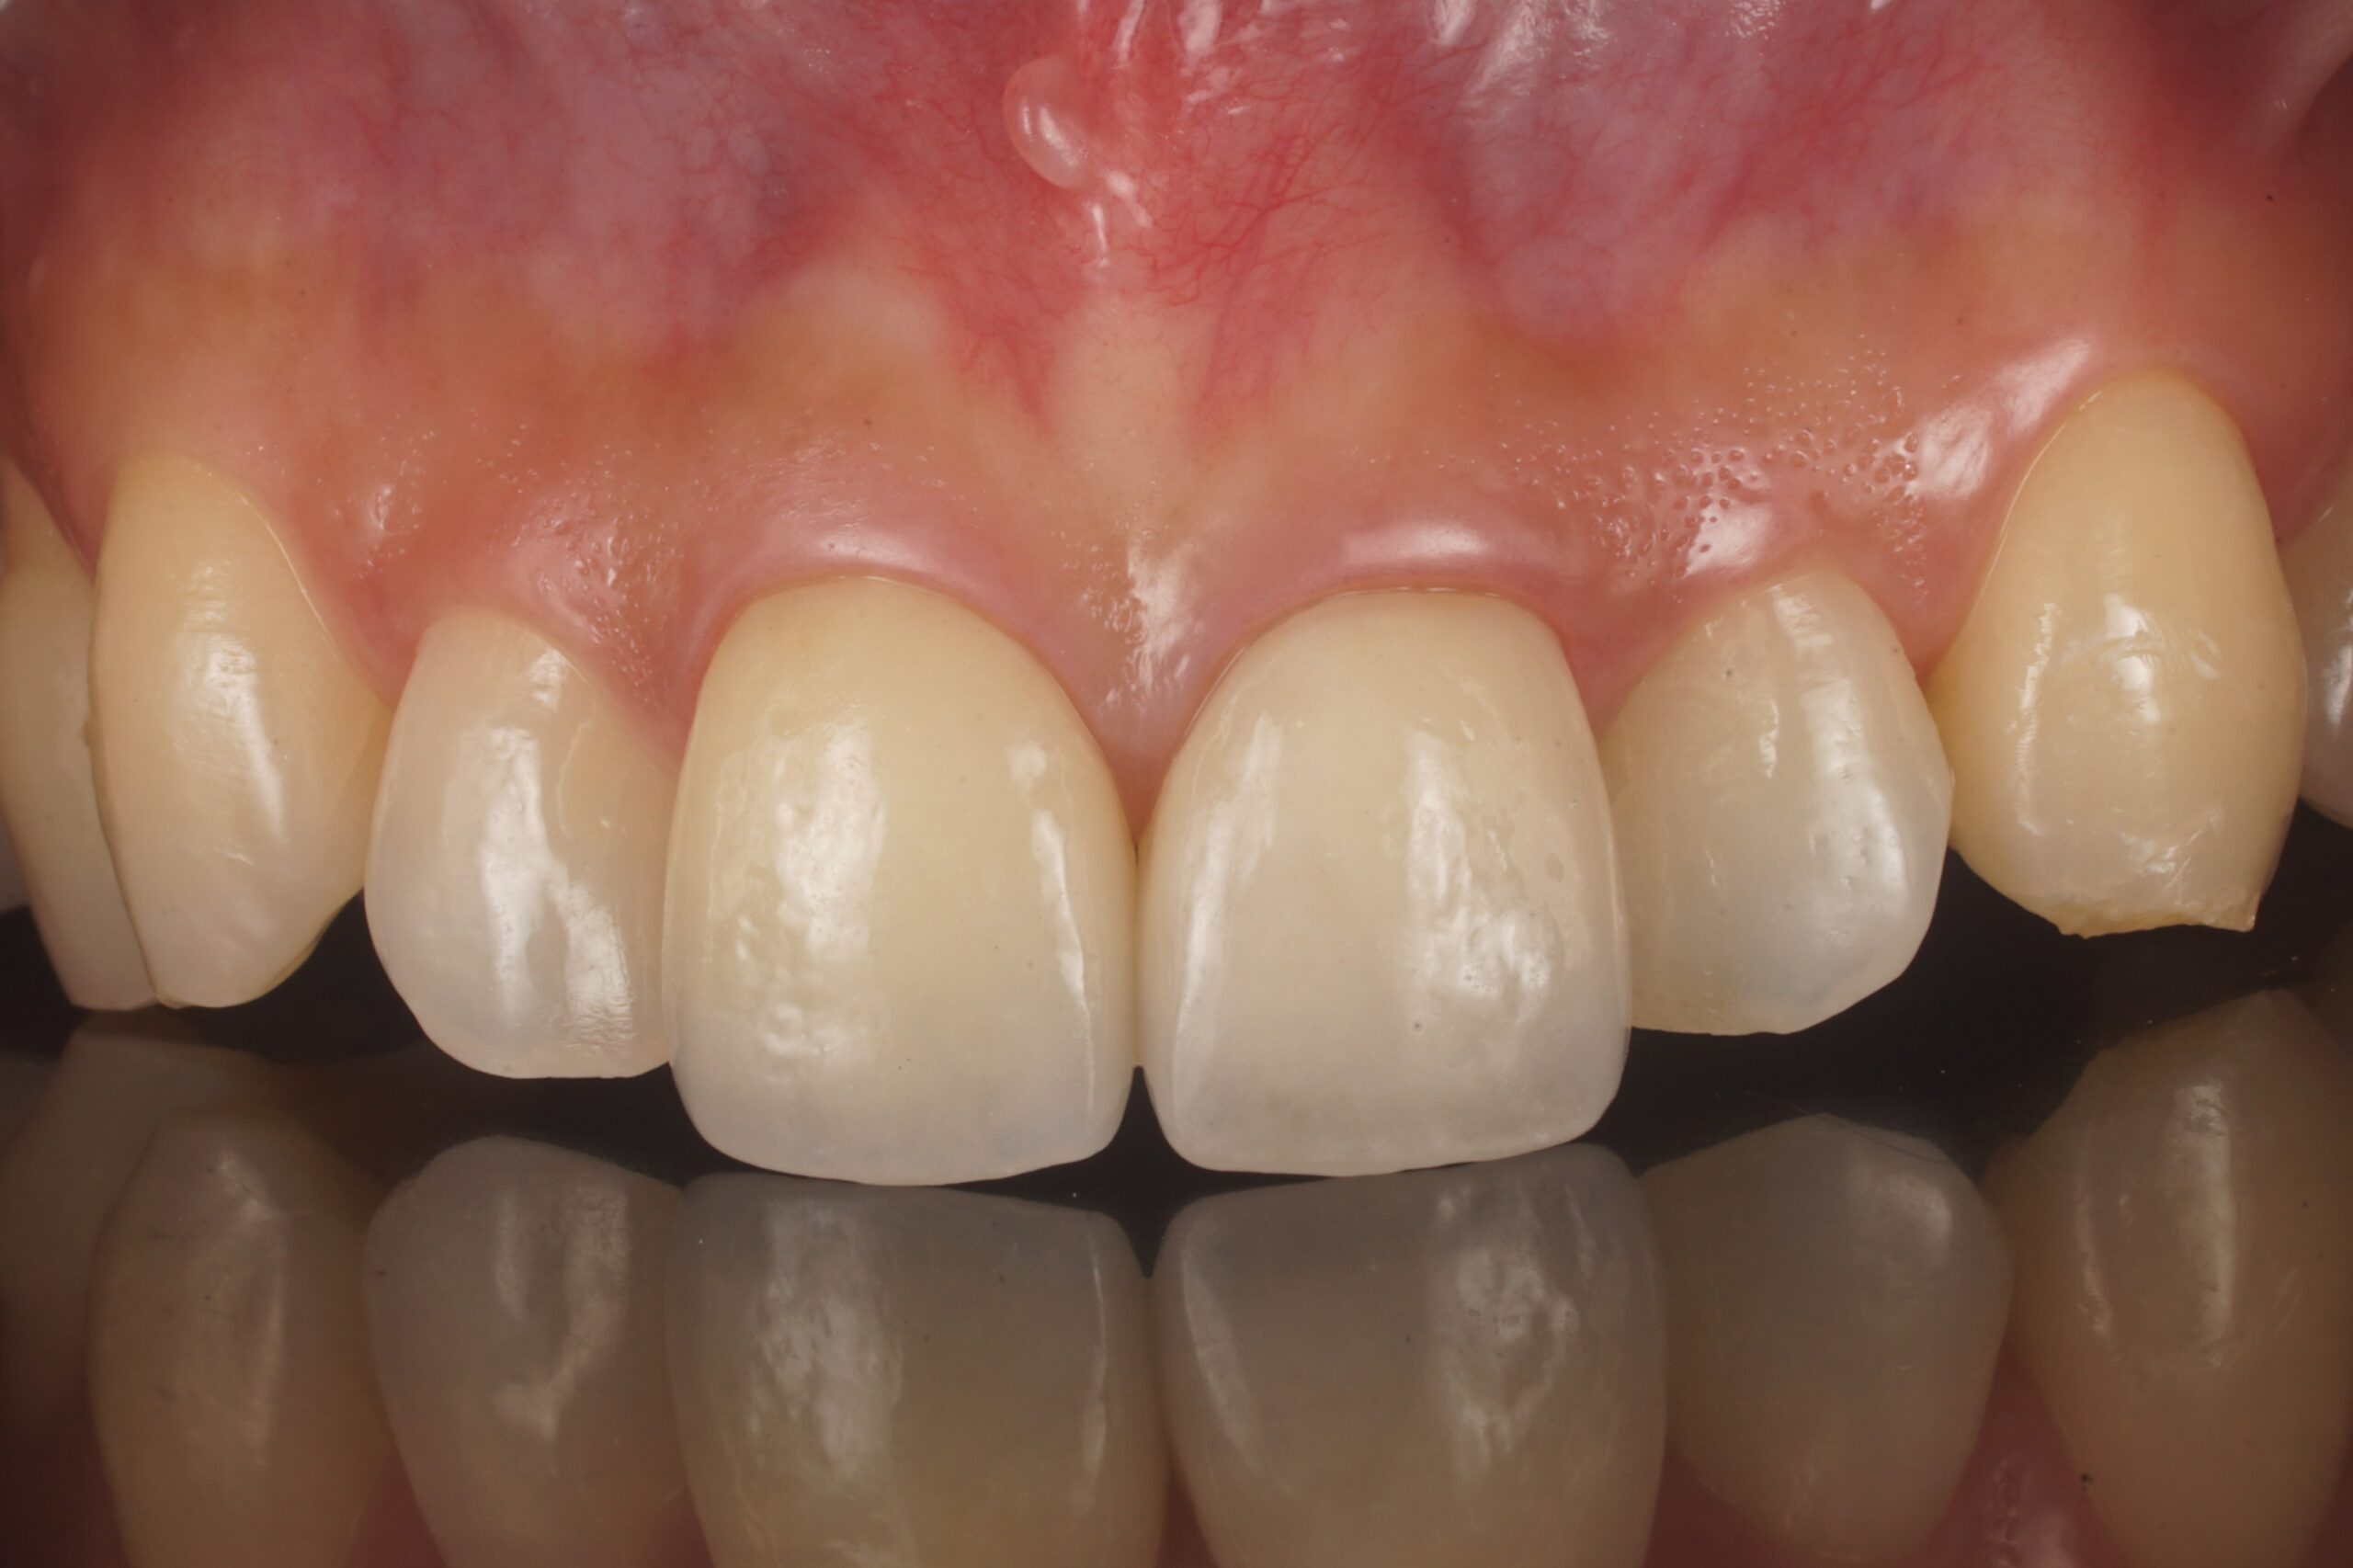

| 治療費 | 総額:560,000円(税抜) 【内訳】 精密根管治療60,000円(前歯)×3、ファイバーポストコア20,000円×3、セラミック治療160,000円×2 |

| ここがこだわりのポイント!☝ | 外傷で歯の神経が壊死しており、変色歯になっていたので、丁寧に根管治療を行ってからセラミックにて審美性の回復を行なっています。 |